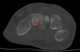

Lucent bone lesion with sclerotic rim

May Be Caused by